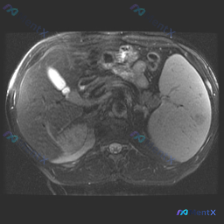

看到一个资料,问题直接指向「脾脏病变」,附上了一张腹部增强CT的横断面图像。整理一下读片和分析思路,这个病例的核心其实不是「找病变」,而是「怎么面对阴性结果」。 病例影像基础信息 - 检查手段:腹部CT横断面,软组织窗 - 增强状态:根据血管及实质强化,考虑为静脉期/平衡期 - 扫描层面:上腹部,包...

整理了一份最近看到的影像读片资料,觉得很有警示意义,发出来和大家一起梳理思路。 --- 基础情况 用户给了一张腹部MRI-T2序列轴位图像,问题预设为“脾脏病变(Splenic lesion)”,同时附带了针对这张图的详细影像分析。 --- 先看这张图给出的客观影像事实 我把这份结构化影像分析的核心...